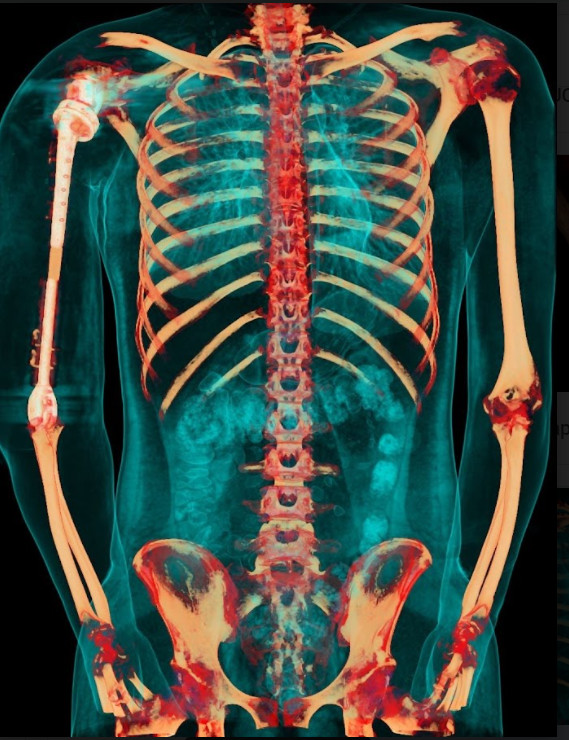

Ảnh chụp X-quang so sánh xương cánh tay 2 bên sau khi phẫu thuật

Việc sử dụng kết hợp 2 loại vật liệu trên cùng một xương nhân tạo để tận dụng được ưu điểm tối đa: tính vận động chính xác, linh hoạt của hợp kim titanium tại vùng khớp, và đặc tính nhẹ, bền, tương thích với cơ thể của vật liệu PEEK. Nhờ vậy, trọng lượng cánh tay nhân tạo có thể giảm xuống còn 1 nửa và chi phí giảm tới hơn 1/3 so với việc chỉ dùng vật liệu kim loại như trước đây.